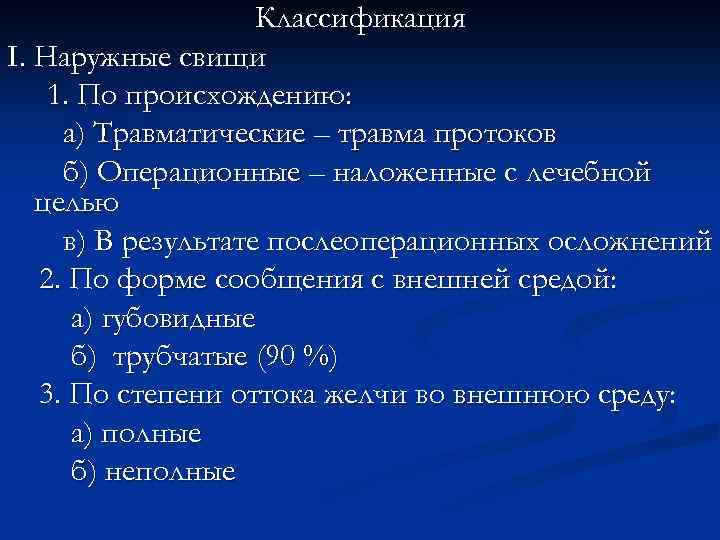

Классификация I. Наружные свищи 1. По происхождению: а) Травматические – травма протоков б) Операционные – наложенные с лечебной целью в) В результате послеоперационных осложнений 2. По форме сообщения с внешней средой: а) губовидные б) трубчатые (90 %) 3. По степени оттока желчи во внешнюю среду: а) полные б) неполные

Классификация I. Наружные свищи 1. По происхождению: а) Травматические – травма протоков б) Операционные – наложенные с лечебной целью в) В результате послеоперационных осложнений 2. По форме сообщения с внешней средой: а) губовидные б) трубчатые (90 %) 3. По степени оттока желчи во внешнюю среду: а) полные б) неполные